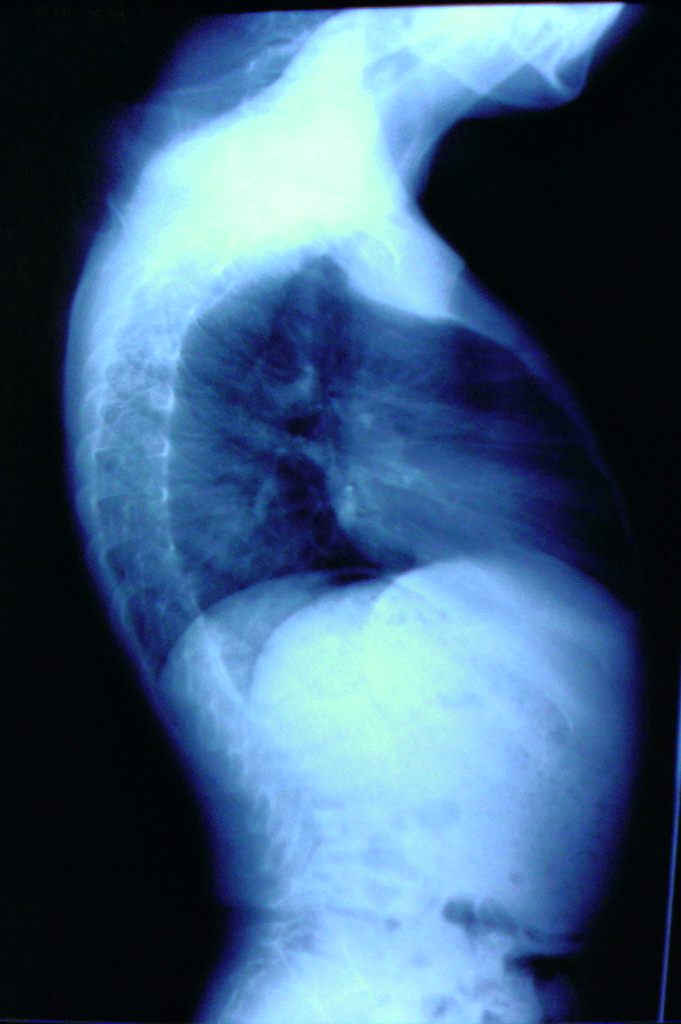

征像:片子的质量也太寒碜了点,也来知道是不是同一个病人的,故且将其当做一个病人分晰下吧。患者男性,年龄应该在10到16岁左右。胸段脊柱明显后突,腰段脊柱明显前突,部分椎体有鸟嘴状改变?髂骨较窄,坐骨大切迹小,髂骨体明显肥大,髋臼缘增生硬化,毛糙,股骨头骨化中心稍有变平,边缘毛糙且密度不均匀,股骨颈粗短,有髋内翻改变。肱骨中段较粗,向下至干骺端变小,肘部各骨骺骨化中心肥大畸形,上尺桡关节对合不良。膝关节骨骺骨化中心肥大畸形,且发育不对称,以股骨内髁为著,胫骨平台骨性关节面稍有硬化,不平整。膝关节有外鄱改变,肘膝部先期钙化带均有密度增高。

意见:考虑原发或者继发的以骺板软骨及关节软骨发育生长异常为主的骨发育生长异常。(个人考虑的病有1大骨节病2粘多糖贮积症及相似病变如脊柱骨骺发育不良及粘脂贮积症3血友病)